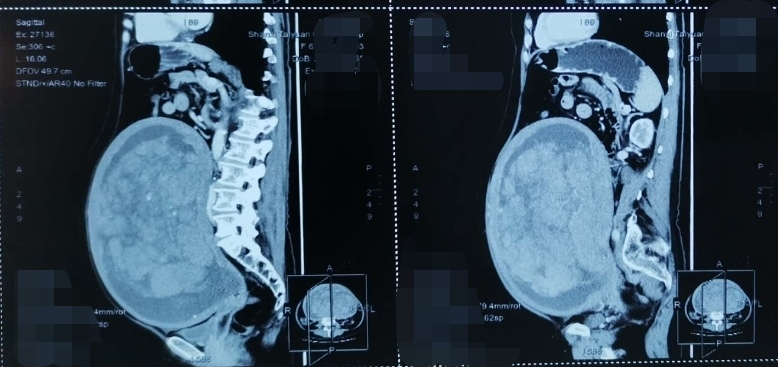

直到前几日,李女士在家人的劝说下在当地医院查彩超时提示:盆内巨大不均质回声(子宫肌瘤囊性变可能,上达剑突下,右侧达腋中线,左侧达腋后线)。得知这一结果,她与家人都惊呆了,病情刻不容缓,巨大的子宫肌瘤对腹腔脏器的压迫,使得她睡眠时无法仰卧,只能侧卧,日常行动也“笨拙”起来。当其家人四处寻访得知太原市中心医院妇科在治疗妇科肿瘤方面经验丰富,而且环境温馨,医护人员亲切热情,于是带着李女士前来就诊。

7月29日,在麻醉手术科的保驾护航下,太原市中心医院妇产科倪妍主任团队为李女士成功切除了直径36厘米、重达16斤的巨大子宫肌瘤。术中止血确切,密切关注患者生命体征,历时1.5小时顺利完成了手术,术中出血少于100ml。

虽然李女士的子宫肌瘤巨大,但手术中快速病理结果显示为良性病变,手术时间短,术中出血少,患者术后恢复良好。